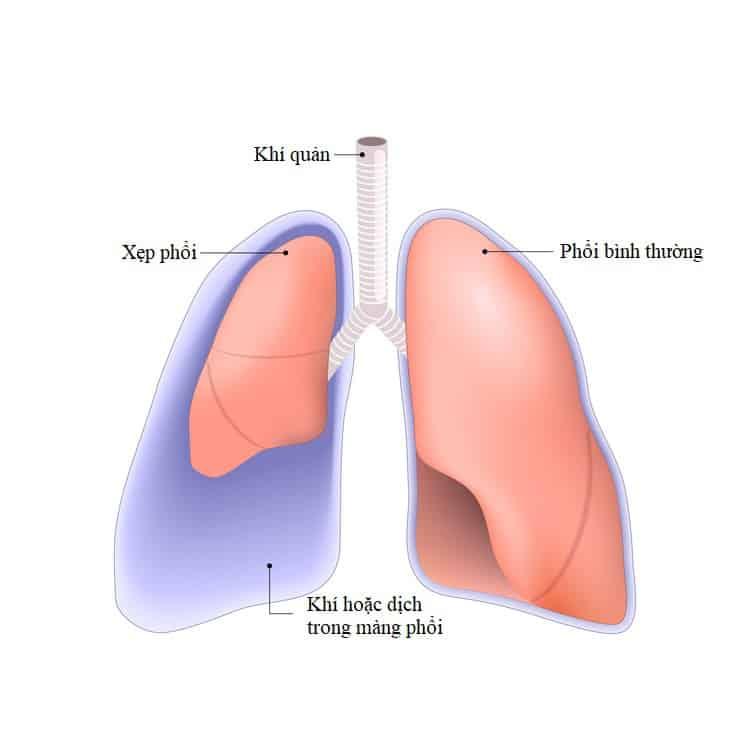

Màng phổi có hai lớp, một lớp bao quanh mỗi lá phổi (màng phổi tạng) và một lớp lót thành ngực (màng phổi thành). Bình thường, vẫn luôn có một lượng dịch nhỏ ở giữa hai lớp màng này để giúp bôi trơn khi phổi nở ra trong lúc bạn hít thở.

Tuy nhiên, một số tình trạng sức khỏe có thể khiến lượng dịch tích tụ quá nhiều, gọi là tràn dịch màng phổi, hay mọi người thường gọi là phổi có nước.

Nếu dịch màng phổi có mủ được gọi là tràn mủ màng phổi, có máu gọi là tràn máu màng phổi.

- Xẹp phổi một phần